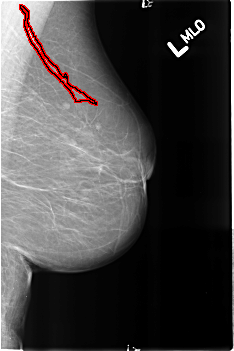

FILE: B_3190_1.LEFT_MLO.OVERLAY

TOTAL_ABNORMALITIES 1

ABNORMALITY 1

LESION_TYPE CALCIFICATION TYPE VASCULAR DISTRIBUTION N/A

ASSESSMENT 2

SUBTLETY 4

PATHOLOGY BENIGN_WITHOUT_CALLBACK

TOTAL_OUTLINES 1

BOUNDARY